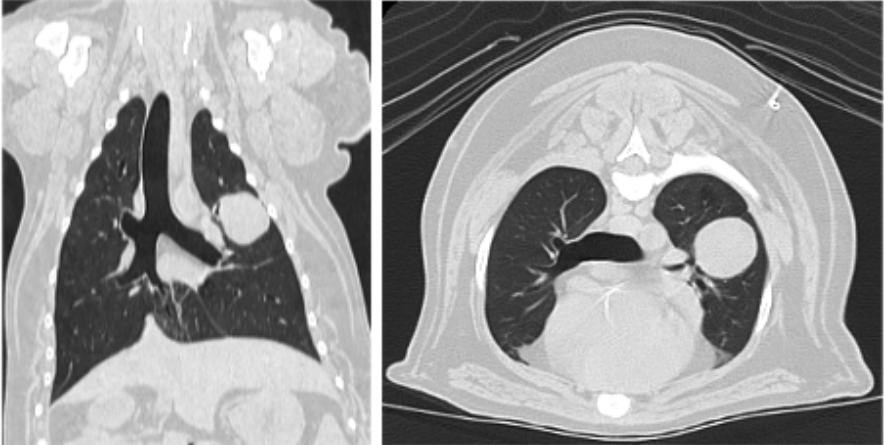

01 영상검사 소견

​정확한 진단을 위해 CT 촬영을 진행하였습니다.

울산 강아지 폐종양 수술 전 CT 결과 / 출처: 에스동물메디컬센터

📌

CT 촬영 결과

✔️ 좌측 폐 전엽에 약 2.6cm 크기의 불규칙한 종괴

✔️ 주변 기관지 일부가 눌려 협착 소견

✔️ 국소 무기폐(atelectasis) 가능성(폐가 정상적으로 펴져 있지 못하고 줄어든 상태)

✔️ 양측 폐 전엽 주변부에 고밀도 결절(노령 변화나 작은 골종 가능성)

✔️ 간과 피부에도 작은 결절 확인

​이러한 소견으로 폐암 가능성이 높아 좌측 전엽 절제술을 계획​했습니다.

⚠️ 영상학적 결과만으로 폐에 국한된 원발성 종양인지, 혹은 다른 장기에서 전이된 것인지 단정하기 어려워 수술적 절제 후 조직검사가 필수입니다.